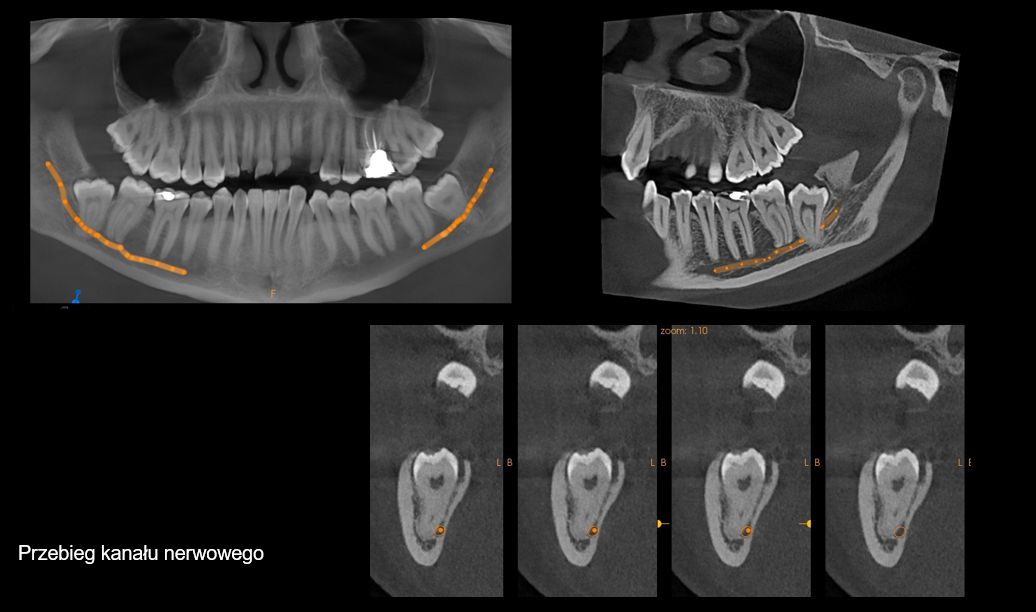

Planowanie implantów

tomografia szczęki w Białymstoku

tomografia szczęki Białystok